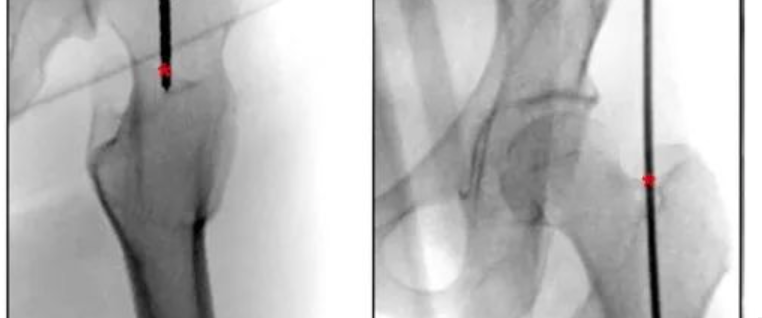

以Gerdy结节为起点,向股骨外侧髁近端作12 cm皮肤切口。识别髂胫束前后缘,经外侧髌旁入路从前外侧窗口显露关节面(图2a)。随后沿髂胫束后缘分离,向前牵开股外侧肌,向后牵开股二头肌(图2b)。尽量避免离断上外侧膝动脉分支。显露外侧髁及干骺端后外侧区域以放置钢板并观察骨折线。为复位骨干,另于股骨前内侧作3 cm切口,行手法复位。关节面、后髁及骨干复位后,以克氏针临时固定。关节面采用6.5 mm空心松质骨螺钉固定,骨干以4.5 mm皮质骨螺钉行拉力螺钉固定。将3.5 mm干骺端钢板(DePuy Synthes,瑞士)预弯后作为后支撑钢板固定后外侧髁(图2c)。随后采用微创钢板接骨术(MIPO)放置LCP-DF钢板(DePuy Synthes,瑞士)作为中和钢板(图2d-e)。

术后X线及CT证实骨折解剖复位,双钢板呈垂直位固定(图3a-e)。